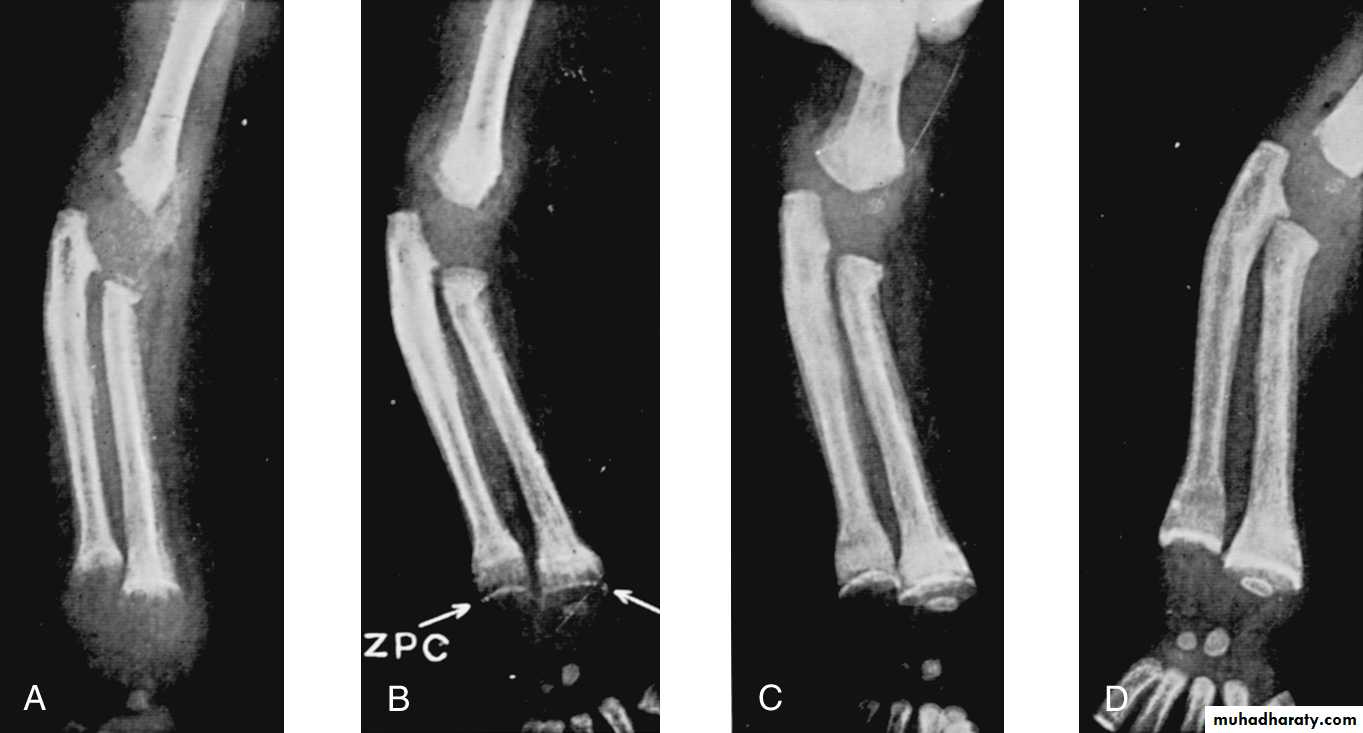

Healing Rickets: Calcification takes place in the zone of preparatory calcification